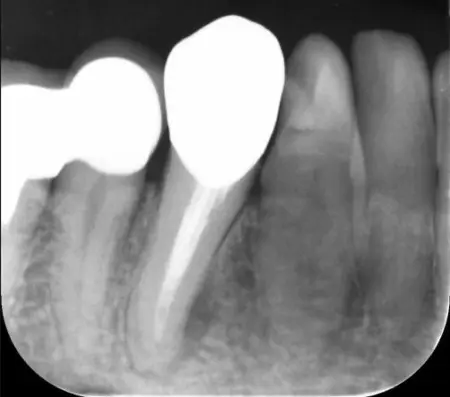

治療前

治療後

レントゲンを撮影して詳しく拝見したところ、痛みが出ている右下前歯の根の周囲には黒い影が見られました。この影は、歯の内部に細菌が侵入して炎症を起こし、歯根の先に膿が溜まる「根尖(こんせん)病変」によるものです。

この歯は以前、細菌感染した神経を取り除き、神経が入っていた細い管「根管」を清掃して薬を詰める「根管治療」を行っていました。根管治療後には被せ物が装着されていましたが、その被せ物が経年劣化した、もしくは根管治療が不十分だったことが原因で、再度細菌が根管内に侵入して炎症を起こしたと考えられます。

まずは装着されている古い被せ物を外し、唾液に含まれる細菌や血が根管内に入るのを防ぐために、ゴム製のシート「ラバーダム」で覆って治療部位だけを露出させます。次にマイクロスコープで確認しながら、感染した部位を丁寧に除去しました。

根管内が清潔になったことを確認し、再び細菌が入り込まないようしっかりと薬を詰めました。

その後は最終的な被せ物を作製するために、歯の形を整えてから型取りを行います。後日、完成したジルコニアクラウンを装着し、噛み合わせに問題がないかをしっかりと確認しました。

治療後は、経過観察のために3ヶ月後と6ヶ月後にレントゲンやCTの撮影をしたところ、歯根周辺にあった根尖病変の影が徐々に小さくなり、歯を支える骨が再生してきていることが確認できたため、治療を終了しています。